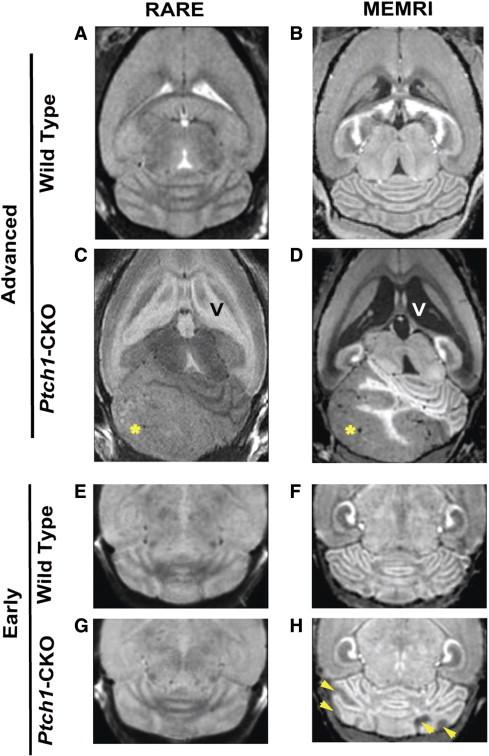

Mouse models have increased our understanding of the pathogenesis of medulloblastoma (MB), the most common malignant pediatric brain tumor that often forms in the cerebellum. A major goal of ongoing research is to better understand the early stages of tumorigenesis and to establish the genetic and environmental changes that underlie MB initiation and growth. However, studies of MB progression in mouse models are difficult due to the heterogeneity of tumor onset times and growth patterns and the lack of clinical symptoms at early stages. Magnetic resonance imaging (MRI) is critical for noninvasive, longitudinal, three-dimensional (3D) brain tumor imaging in the clinic but is limited in resolution and sensitivity for imaging early MBs in mice. In this study, high-resolution (100 μm in 2 hours) and high-throughput (150 μm in 15 minutes) manganese-enhanced MRI (MEMRI) protocols were optimized for early detection and monitoring of MBs in a Patched-1 (Ptch1) conditional knockout (CKO) model. The high tissue contrast obtained with MEMRI revealed detailed cerebellar morphology and enabled detection of MBs over a wide range of stages including pretumoral lesions as early as 2 to 3 weeks postnatal with volumes close to 0.1 mm(3). Furthermore, longitudinal MEMRI allowed noninvasive monitoring of tumors and demonstrated that lesions within and between individuals have different tumorigenic potentials. 3D volumetric studies allowed quantitative analysis of MB tumor morphology and growth rates in individual Ptch1-CKO mice. These results show that MEMRI provides a powerful method for early in vivo detection and longitudinal imaging of MB progression in the mouse brain.